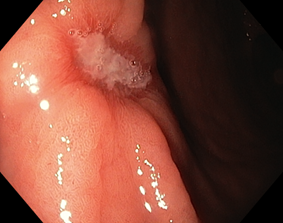

Эндоскопическая классификация стадий течения язвенного процесса по Sakita-Miwa

|

A1 |

H1

S1

A2

H2 |

S2 |

Рисунок 1. Стадии регрессии (заживления) язвы желудка и их характерные черты:

A (Active). Активная стадия (обострение)

A1. Слизистая оболочка, окружающая язву, выглядит набухшей в результате отёка, регенерация эпителия отсутствует.

A2. Отёк слизистой оболочки вокруг язвы уменьшился, край язвы отчётливо виден и в крае язвы появились первые ростки регенерирующего эпителия. По периметру язвы часто прослеживается красный ободок, а непосредственно по краю – циркулярный белый струп. Обычно, сходящиеся складки слизистой оболочки прослеживаются вплоть до края язвы.

H (Healing). Стадия заживления

H1. Слой белого фибрина, покрывающий язву, становится тонким, а регенерирующий эпителий распространяется непосредственно на основание язвы. Градиент между краем и дном язвы сглаживается. Но кратер язвы все еще очевиден, и край язвы отчётливо виден. Диаметр язвенного дефекта составляет примерно от половины до двух третей диаметра язвы в стадии A1.

H2. Язвенный дефект меньше, чем в стадии H1, и регенерирующий эпителий покрывает большую часть дна язвы. Площадь слоя белого фибрина составляет примерно от четверти до трети площади язвы в стадии А1.

S (Scarring). Стадия рубца

S1. Регенерирующий эпителий полностью покрывает дно язвы. Белый слой фибрина полностью исчез. Первоначально зона регенерации выглядит ярко красной. При прицельном осмотре можно увидеть большое количество капилляров. Сформировался "красный рубец".

S2. В срок от нескольких месяцев до нескольких лет исходно красный рубец принимает цвет окружающей слизистой оболочки. Сформировался «белый рубец».

Комментарий. Плановое эндоскопическое исследование подтверждает наличие язвенного дефекта, уточняет его локализацию, форму, размеры, глубину, состояние дна и краев язвы, позволяет выявить признаки пенетрации, рубцовой деформации и стенозирования просвета органа. Плановое эндоскопическое исследование дает возможность обнаружить другие сопутствующие изменения слизистой оболочки и определить нарушения гастродуоденальной моторики. Для оценки стадии язвенного процесса (обострение, заживление, рубцевание) целесообразно использовать общепринятую в мире классификацию Sakita-Miwa (рис.1).